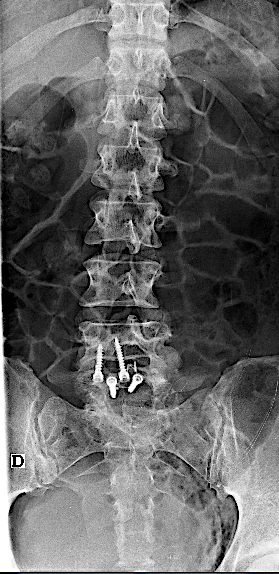

Paciente de 34 años con lumbalgia mecánica refractaria de años de evolución con progresión de la clínica.

Obsérvese el incremento de la lisis de la pars en las RX dinámicas. La paciente no presentaba clínica radicular significativa por lo que se optó por ALIF L5-L6. El disco L4-L5 presentaba un grado bajo de degeneración.

Tras retirada de faja, la paciente seguía presentando lumbalgia mecánica. Obsérvese la lisie de la pars.